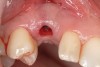

Ten weeks after implant insertion, the patient presented to begin soft-tissue contouring via a fixed, provisional crown (Figure 10). Deliberate under-contouring of the cervical portion of the temporary restoration was performed to avoid unwanted mucosal recession and possible esthetic complications (Figure 11 and Figure 12).

Figure 10   Soft-tissue contouring 10 weeks after implant insertion.

Figure 10

Figure 11  Temporary restoration.

Figure 11